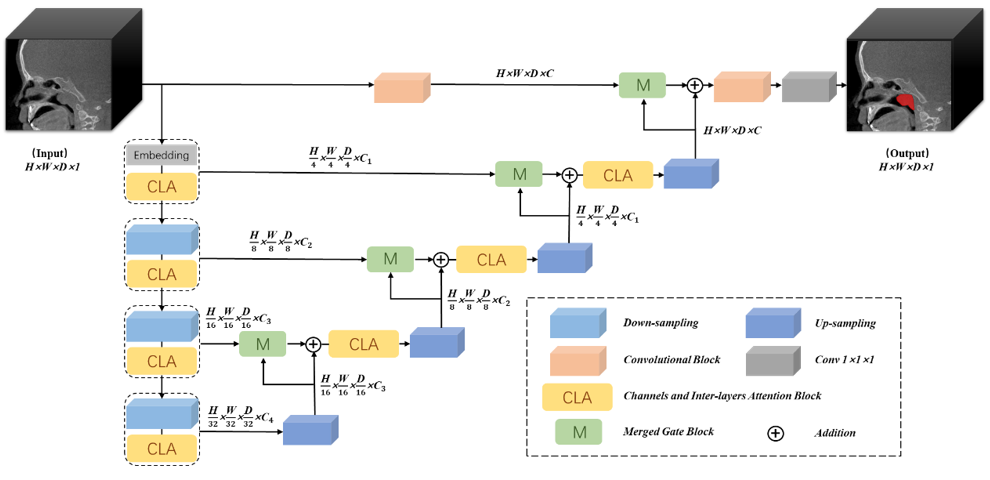

对于这个情况,团队的解决思路是参考Merged UNet中的合并门的做法,设计了合并块。另一个就是分割面不够平滑、均匀。对此,团队在设计的CLA块中,将从图像三个方向进行层与层之间的注意力操作,从而增加了空间上的深度信息。

基于以上两点设计,深圳大学 “腺形智消”团队创新地设计了一种新的分割模型:

几何边界与分割边界的不一致:UNet的结构中存在上采样和下采样的过程。团队认为在下采样中得到的特征具有原始图像的几何轮廓信息,在上采样中得到的特征更多的是分割目标的信息。而团队在训练模型中发现模型的分割的结果总是会被几何轮廓所影响。而这种影响在此任务中是需要去避免的。对此,团队认为模型应该对下采样中的轮廓信息进行特征信息补充与修正,从而减少轮廓对分割结果的不良影响。为了达到这样的目的,团队参考Merged UNet中合并门的结构设计,针对3D医学图像处理任务重新设计了合并块。

丰富的层间空间特征:存在整体的分割结果后界不光滑的情况,团队改进了UNETR++的EPA块,使模型能学习到更多空间的特征,并增强层与层之间的关系。其中,仍然保留了EPA中空间与通道特征结合的思想,但是又强调了层与层的空间特征。于是,将双头注意力扩展为四头注意力,其中三个头分别是3D图片长宽高三个维度的。为了强调这三个维度之间存在空间上的强相关性,对应的三个注意力将共享相同的Q、K矩阵。团队不认为空间与通道具有强相关性。而UNETR++,团队的通道维度不与空间维度进行参数共享。